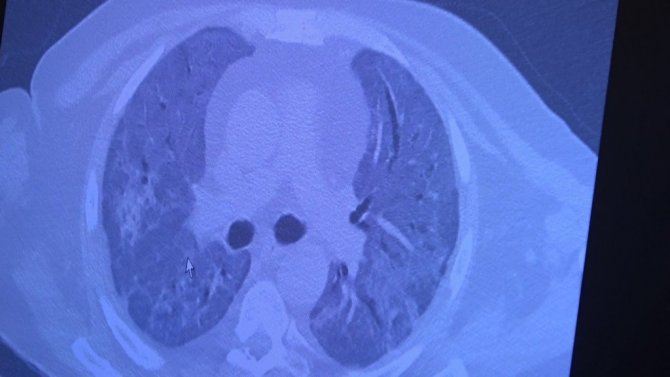

Yaşlı ile genç vatandaşın akciğerlerindeki aşı farkı

70 yaşında aşı olmuş ve korona virüse yakalanmış biri ile 49 yaşında aşı olmamış ve korona virüse yakalanmış kişilerin akciğer tomografilerini inceleyen Prof. Dr. Özkaya, "Sizin gerçek yaşam verilerinden bir örnek vermek istiyorum. 70 yaşında bir teyzemiz, iki doz aşısını olduktan sonra Covid- 19'a yakalanıyor. Çok hafif akciğer tutulumu ile evinde bunu rahatlıkla atlatıyor. Tedavisini evde yapıyoruz. 70 yaşında olmasına rağmen bu hastalığı çok hafif atlattı. Bu aşının teyzemiz üzerinde yüzde 100 koruyuculuğu var. Yoğun bakıma yatmadı. Hastalığı evinde geçiriyor. Bu, aşının avantajıdır. Aşı olmamış 49 yaşında genç bir hastamızın akciğerine baktığımızda ise neredeyse hiç akciğeri kalmamış, her tarafı neredeyse yanmış. Covid-19'a bağlı harabiyet var. Hayatını zor kurtardık" şeklinde konuştu.